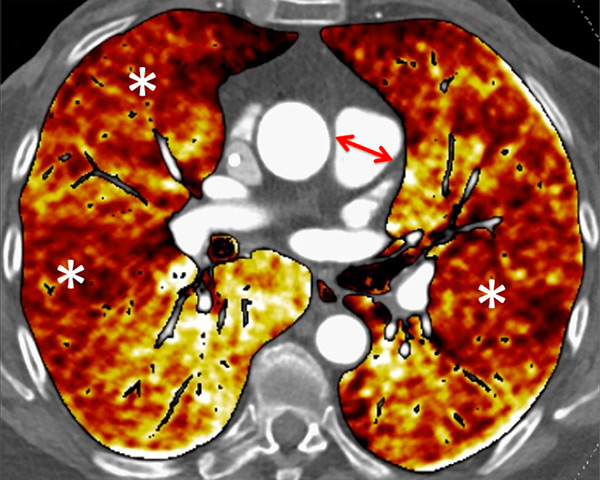

Figure 7

Portopulmonary hypertension in a 16-year-old. No abnormalities were found on morphological computed tomography (A/B), but heterogeneous perfusions were present on the perfusion map (stars, C/D).